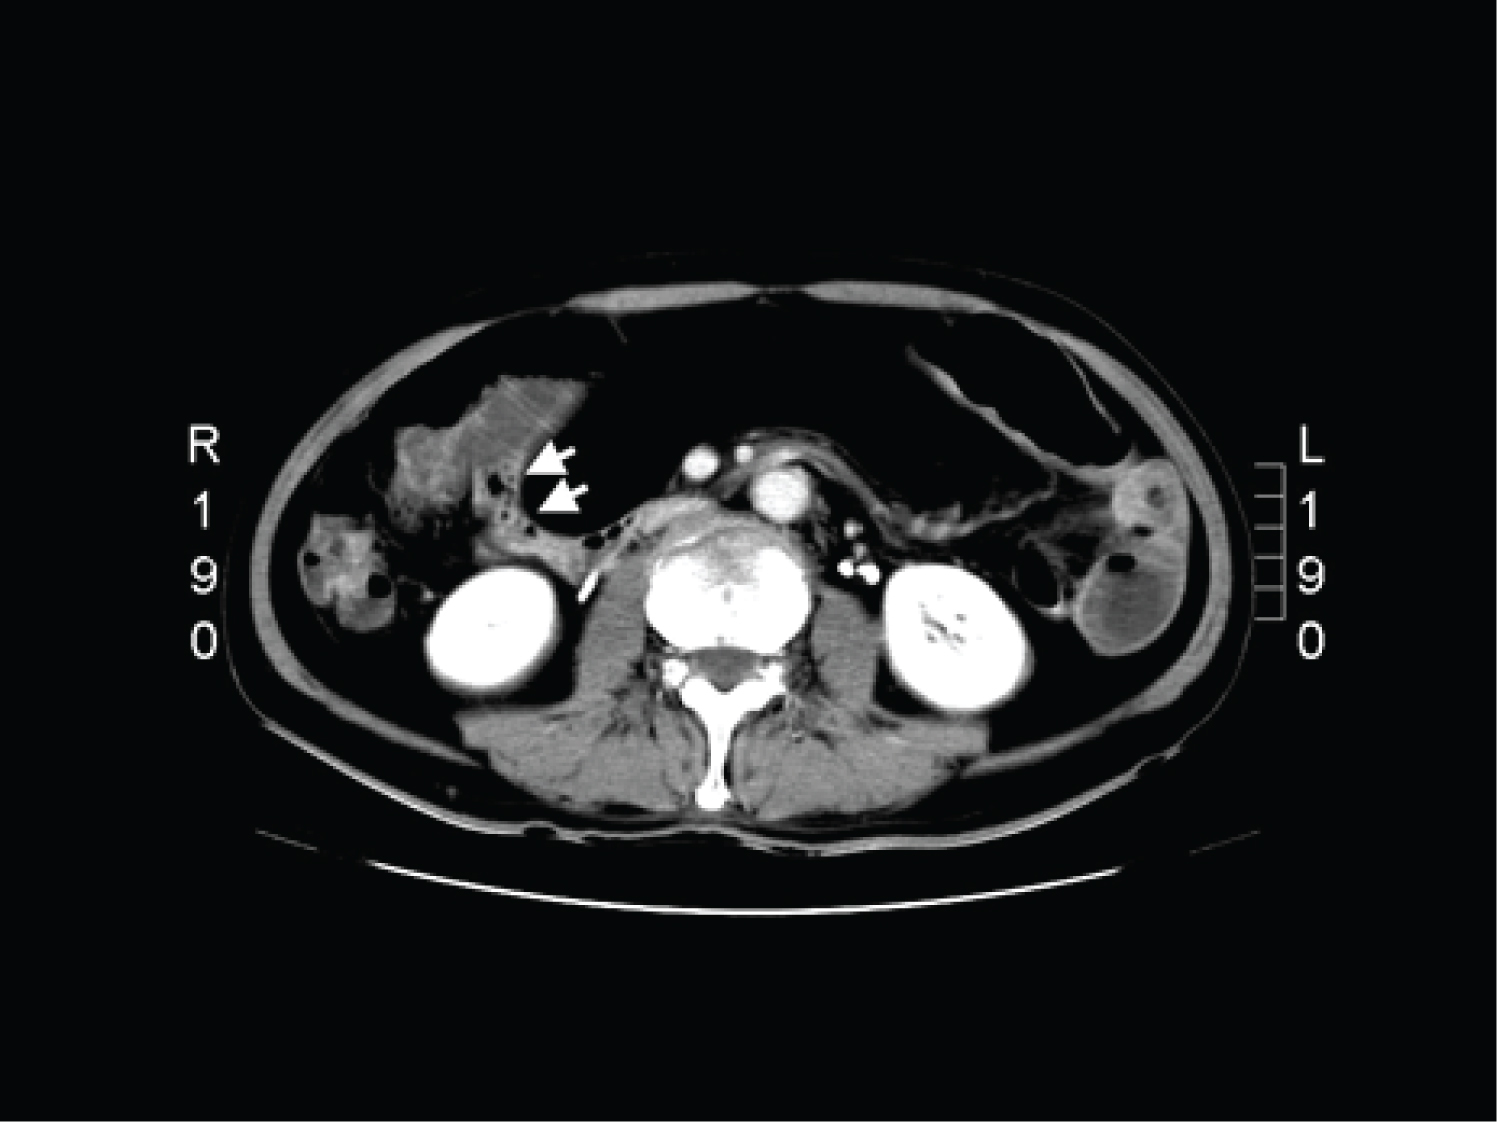

In our emergency room, physical examination revealed, diffuse tympanic sound while percussion. General laboratory examinations were in normal range. Abdominal plain film showed suspicious of a radiolucent mass (Figure 1, black arrow) and the bowel loops were displaced up and down. The proximal jejunum was dilated (Figure 1, white arrow). Ultrasound of abdomen showed a hypoechoic mass well-margin (Figure 2, arrow). Computed tomography (CT) of abdomen showed a mass-like lesion compressed the intestine and caused proximal bowel loops dilated (Figure 3, arrow). Initially, we though the mass-like lesion as free air. After adjustment of the contrast of CT, we found an encapsulated fatty component mass-like lesion over the mesentery in the lower abdomen (Figure 4, arrow).

Figure 3: Computed tomography (CT) of abdomen showed a hypodense lesion compressed the intestine and caused proximal bowel loops dilated (arrow). View Figure 3

Figure 4: Computed tomography (CT) of abdomen: Initially, we though the mass-like lesion as free air. After adjustment of the contrast of CT, we found an encapsulated fatty component mass-like lesion over the mesentery in the lower abdomen (arrow). View Figure 4

The small tumors may not easily been detected by X-ray and ultrasound. Emergency abdominal CT is now the most common way of identifying extraluminal or intraluminal lesions causing small bowel obstruction [3]. However, we have to check the contrast number of abdominal CT. In Figure 3, we initially misunderstood the lipoma as free air. After adjusting the contrast number shown in Figure 4, we could see a fat contain mass-like lesion. Clinician should pay more attention to the well-defined margin lesion to prevent from misdiagnosis.